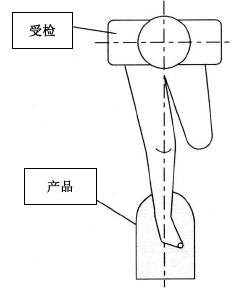

一、跟骨密度儀檢測時,耦合劑的涂抹位置

在受檢者的足跟上涂抹耦合劑時,是為了除去油囊和受檢者的足跟之間殘留的空氣,在足跟上涂抹充分的耦合劑,確保受檢部位與油囊接觸部位完全被覆蓋。

正確超聲耦合劑充分用量及位置

檢測時,足緊貼于產品的最下端(如圖緊貼3個部位)。 骨密度儀的護腿板與足軸和身體的中心軸,需呈一條直線。

跟骨骨密度檢測正確坐姿示意圖